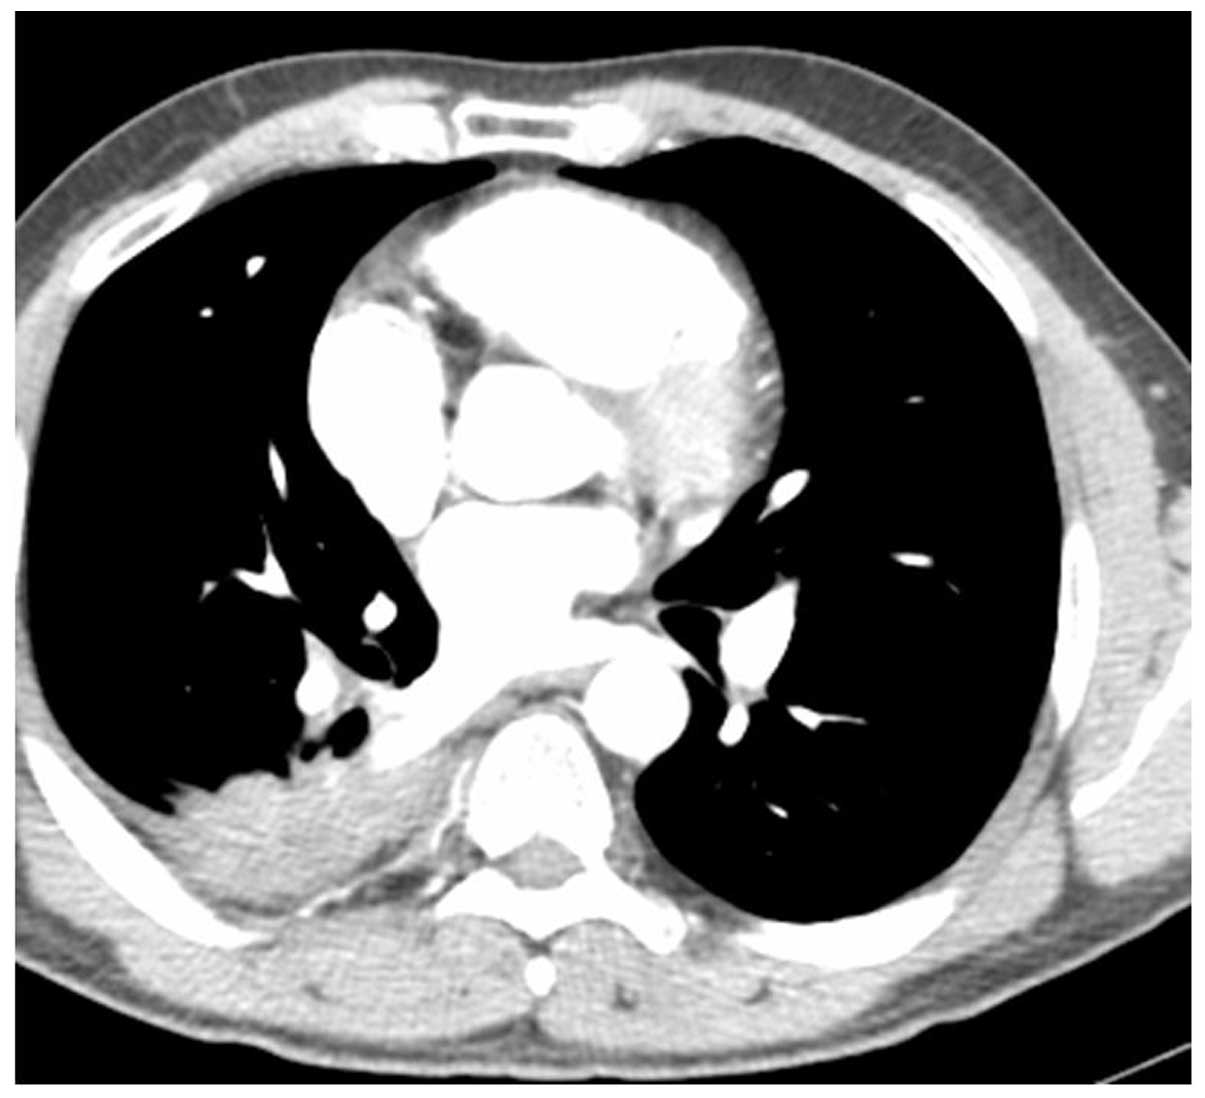

lung cancer ct colon figure ol hyponatremia

Metastasis To The Colon From Lung Cancer Presenting With Severe

Metastasis to the colon from lung cancer presenting with severe www.spandidos-publications.com